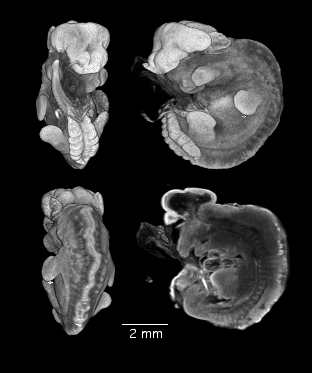

Magnetic resonance imaging of a mutant embryo with a malformed brain and failure of neural tube closure. Embryo courtesy of Elwood Linney.

MRI of malformed mouse embryo